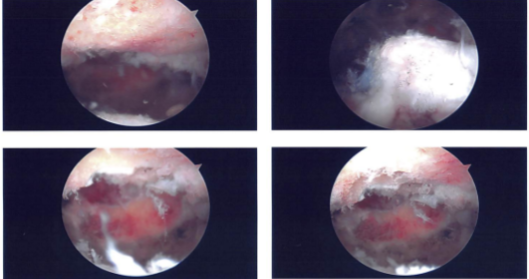

A lateral entry portal was made for the repair of the rotator cuff. The debridement of the rotator cuff was done. Also, the superior surface of the head of humerus was cleaned and debrided with the use of burr for the preparation for the repair of the rotator cuff.

Triple play Corkscrew bioabsorbable corkscrew from Arthrex was used and inserted into the head of the humerus. The six tails of the three sutures of the anchor were passed through the rotator cuff tendon sequentially and tied on to each other in the form of the horizontal mattress.

Good apposition and repair of the rotator cuff was achieved. The sutures were cut. Final pictures were taken and saved. The shoulder was thoroughly irrigated and drained. Arthroscope was removed and the patient’s arm was taken out of traction. A subpectoral approach was planned for the biceps tenodesis.

Intraoperative images